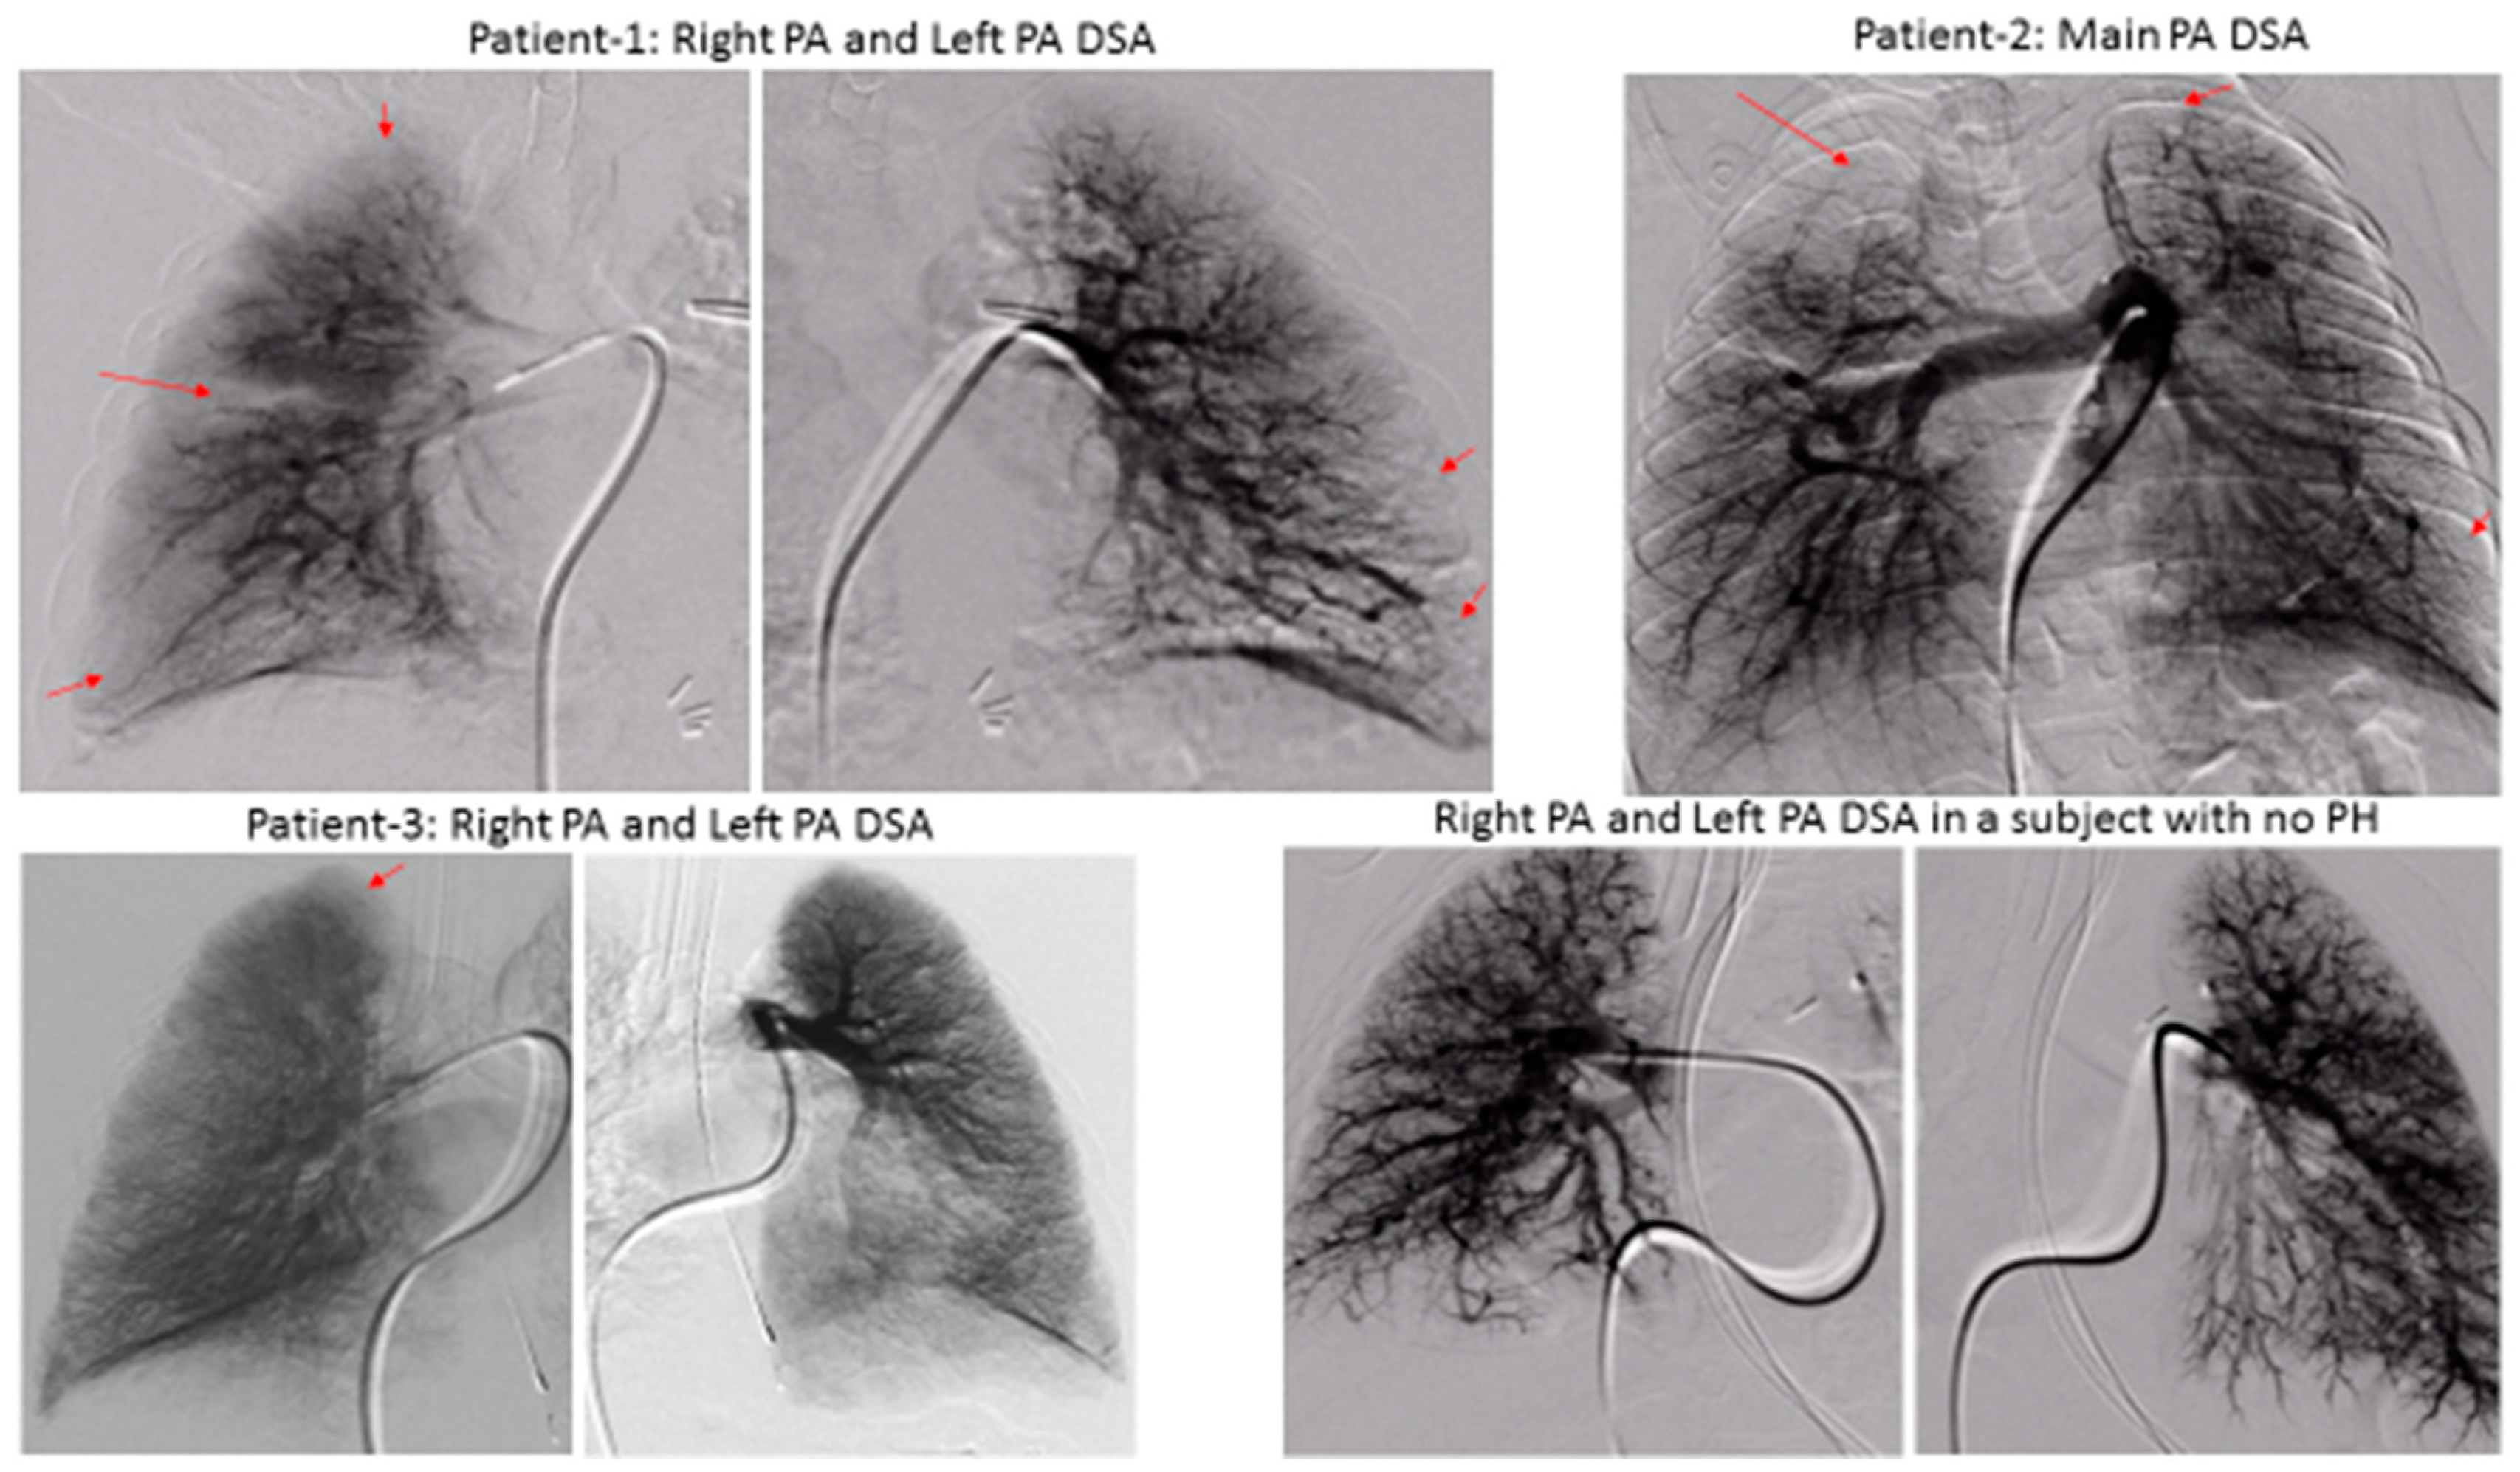

We demonstrated significant lung perfusion defects using DSPA in all three patients and compared those results with DSPA images of a normal child with normal pulmonary artery pressure (Figure 2). Patients 1 and 2 had more segmental perfusion defects than patient 3. The mean pulmonary artery pressure to mean aortic pressure ratios in patients 1, 2, and 3 were 54%, 55%, and 43%, respectively. Similarly, the pulmonary vascular resistance index to systemic vascular resistance index ratios in patients 1, 2, and 3 were 0.36, 0.31, and 0.25, respectively (Table 1). Although, these are only three patients, the preliminary data suggest that a severe perfusion abnormality correlates to the severity of pulmonary vascular disease in children with BPD. However, larger studies will be necessary to draw final conclusions.

Figure 2.

Digital Subtraction Pulmonary Angiography showing segmental perfusion defects (capillary phase, pointed by arrows) in three patients versus a normal subject with no pulmonary hypertension. (PA: pulmonary artery, DSA: digital subtraction angiography, PH: pulmonary hypertension).